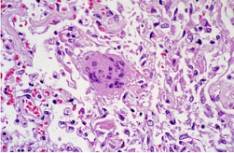

病理標本的(de)一種,制作時將部分(fen)有病變的組織或臟器經過各種化學品和埋(mai)藏法的處理(li),使之固定(ding)硬化,在切片機(ji)上(shang)切成薄片,粘附(fu)在玻片上(shang),染以各種顏色,供(gong)在顯(xian)微鏡(jing)下檢查,以觀察病理(li)變化,作出病理(li)診斷,為臨床診斷和治療提供(gong)幫助。

常用的染色方法是蘇木素-伊紅(Hematoxylin-Eosin)染色法,簡稱H.E染色法。這種方法對任何固定液固定的組織和應用各種包埋法的切片均可使用。蘇木素是一種堿性染料,可使組織中的嗜堿性物質染成藍色,如細胞核中的染色質等;伊紅是一種酸性染料,可使組織中的嗜酸性物質染成紅色,如多數細胞的胞質、核仁等在H.E染色的切片中均呈紅色。